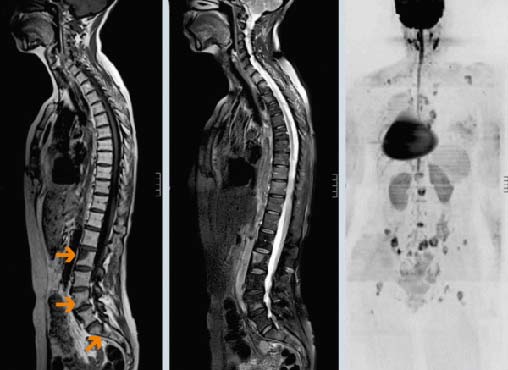

Первичные опухоли позвоночника встречаются редко. Как показывает статистика, до 90% злокачественных новообразований позвоночного столба — это метастазы рака, находящегося в других органах.

Многие типы рака метастазируют в кости, чаще всего в позвонки. В большинстве случаев опухолевые клетки распространяются гематогенно — с током крови. Вторичные очаги ослабляют костную ткань, это грозит патологическими переломами позвонков, которые приводят к сильным болям, существенному снижению качества жизни, сдавлению спинного мозга и нервных корешков.

В 95% случаев метастазы в позвоночнике являются экстрадуральными, то есть находятся за пределами твердой мозговой оболочки. Более чем в половине случаев очаги локализуются на разных уровнях позвоночного столба.

Диагностика метастазов в позвоночнике

Основные методы диагностики — КТ и МРТ. Они помогают детально визуализировать структуры позвоночного столба, опухолевую ткань. Рентгенография менее информативна, так как на снимках видны только костные структуры, обычно ее применяют при подозрении на патологический перелом.